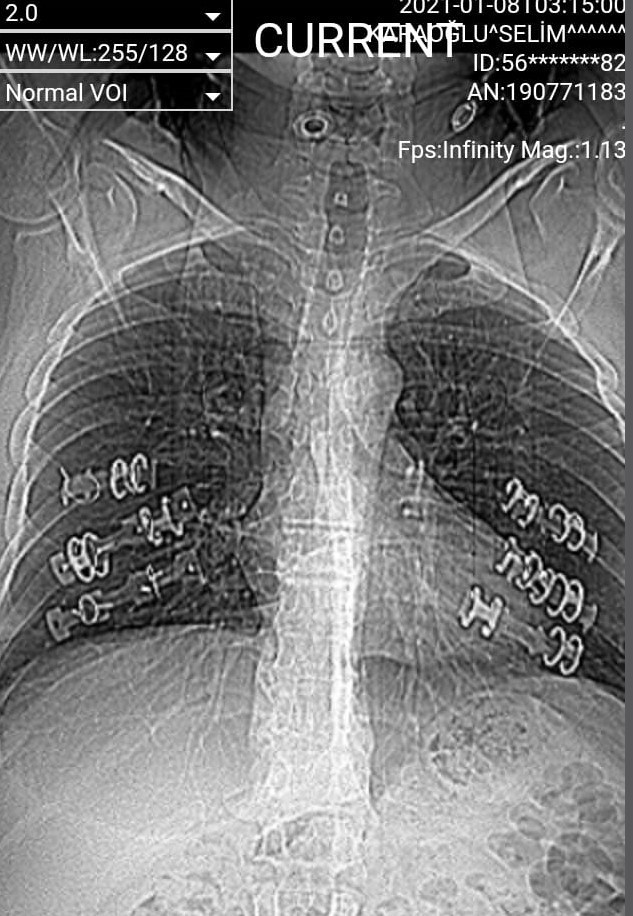

Şiddetli öksürükler ile birlikte kaburgasında ciddi boyutta kırıklar tespit edilen Karaoğlu’na platin ve teller takıldı. Yapılan platin tedavisinin başarısız olması sonrası Karaoğlu’nun vücudunda başlayan kanamalar ile birlikte şişlikler meydana geldi.

Şiddetli öksürükler esnasında kaburgalarının kırıldığını hissettiğini belirten Selim Karaoğlu, “Geçtiğimiz yıl şiddetli öksürüklerim sonrası 6 kaburgam kırıldı. İlk gittiğimde korona virüsten şüphelendikleri için tedavim gecikti. 5 ay boyunca kırık kaburgalarla gezdim. Başka bir hastaneye gidince gerçek ortaya çıktı ve ameliyat oldum. Toplamda dört ameliyat geçirdim. Ameliyatlarda taktıkları platinler tutmadı, bağladıkları tel koptu. Şu an hiçbir doktor benim tedavime yaklaşmak istemiyor. Platinler etkisini kaybedince kanamalar oluyor. Sırt bölgemde şişlikler oluştu. Ben sağlığıma yeniden kavuşmak için yardım bekliyorum” dedi.